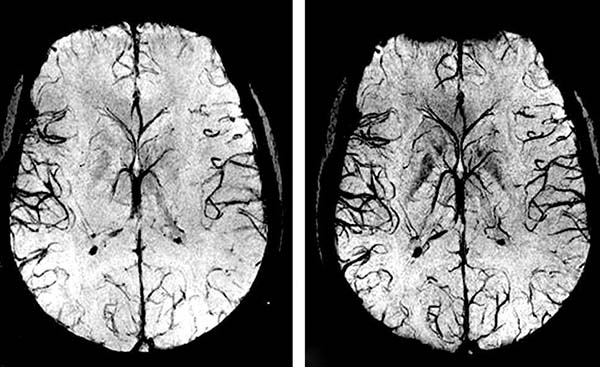

Durante 1 curso de toma de Hyper Cardio, los vasos sanguíneos se fortalecen en un 98,71%.

La circulación sanguínea se restaura sistémicamente – en todos los vasos, arterias y capilares.

Hyper Cardio es la innovación, el orgullo de nuestros científicos. Proporciona casi el 100% de limpieza vascular gracias a su "fórmula inteligente".